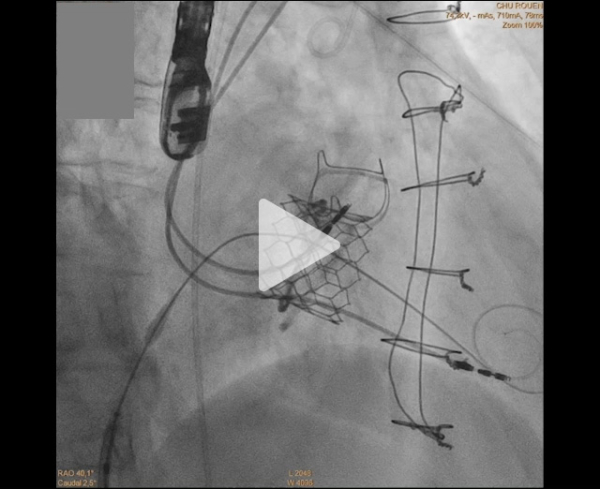

Prise en charge retenue : TMVI valve in ring + LAMPOON

Chez cette patiente à haut risque chirurgical, une chirurgie tridux a été jugée à risque.

Le mécanisme de fuite ne permettait pas une réparation par clip. La présence d’un anneau mitral prothétique rendait envisageable un TMVI valve-in-ring, mais le risque d’obstruction du LVOT était jugé majeur.

Afin d’éviter cette complication, la stratégie retenue a été un TMVI associé à une LAMPOON (Laceration of the Anterior Mitral leaflet to Prevent Outflow Obstruction).

Implantation TMVI Valve SAPIEN 3